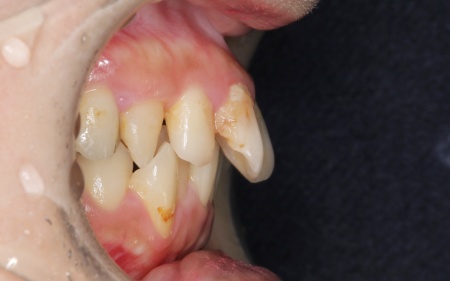

20代女性 ワイヤー矯正で歯並びを整えて虫歯治療やインプラント治療で口腔内全体を改善した症例

詳しく拝見したところ、下の前歯4本を除くほぼすべての歯に虫歯が認められました。 また、左上奥歯1本と左下奥歯1本が欠損しており、その影響で噛み合わせのバランスが崩れているため、噛んだときの痛みにつながっていると考えられます。 このまま放置すると、虫歯が進行したり、欠損部周囲の歯が動いて噛み合わせがさらに不安定になったりするリスクがあるため、虫歯を含めた口腔内全体の治療が必要だと診断しました。 |

診断結果をお伝えしたうえで、以下2つの治療方法を提案しました。 ①歯並びを整えず、必要な部分のみを治療する方法 ②矯正治療で歯並びと噛み合わせの土台を整えたうえで、口腔内全体の治療を行う方法 それぞれのメリット・デメリットをお伝えしたところ、患者様は②の矯正治療を含めた総合的な治療を行う方法を選択されました。 はじめに、歯の表面にブラケットと呼ばれるボタン状の装置を接着し、そこにワイヤーを通して歯を動かすワイヤー矯正を開始しました。治療期間中は定期的に状態を確認し、計画通りに歯が動くよう調整を重ねています。 虫歯が生じている歯に対しては、虫歯部分を丁寧に除去し、歯の形を整えました。その後、被せ物を作製するために型取りを行い、後日完成した被せ物を装着しました。 また、欠損していた左上奥歯1本と左下奥歯1本に対しては、インプラント治療を行います。 すべての治療工程を終えたあと、噛み合わせや見た目、被せ物の使用感に問題がないかなどを確認して、治療を終了しています。 |

治療前